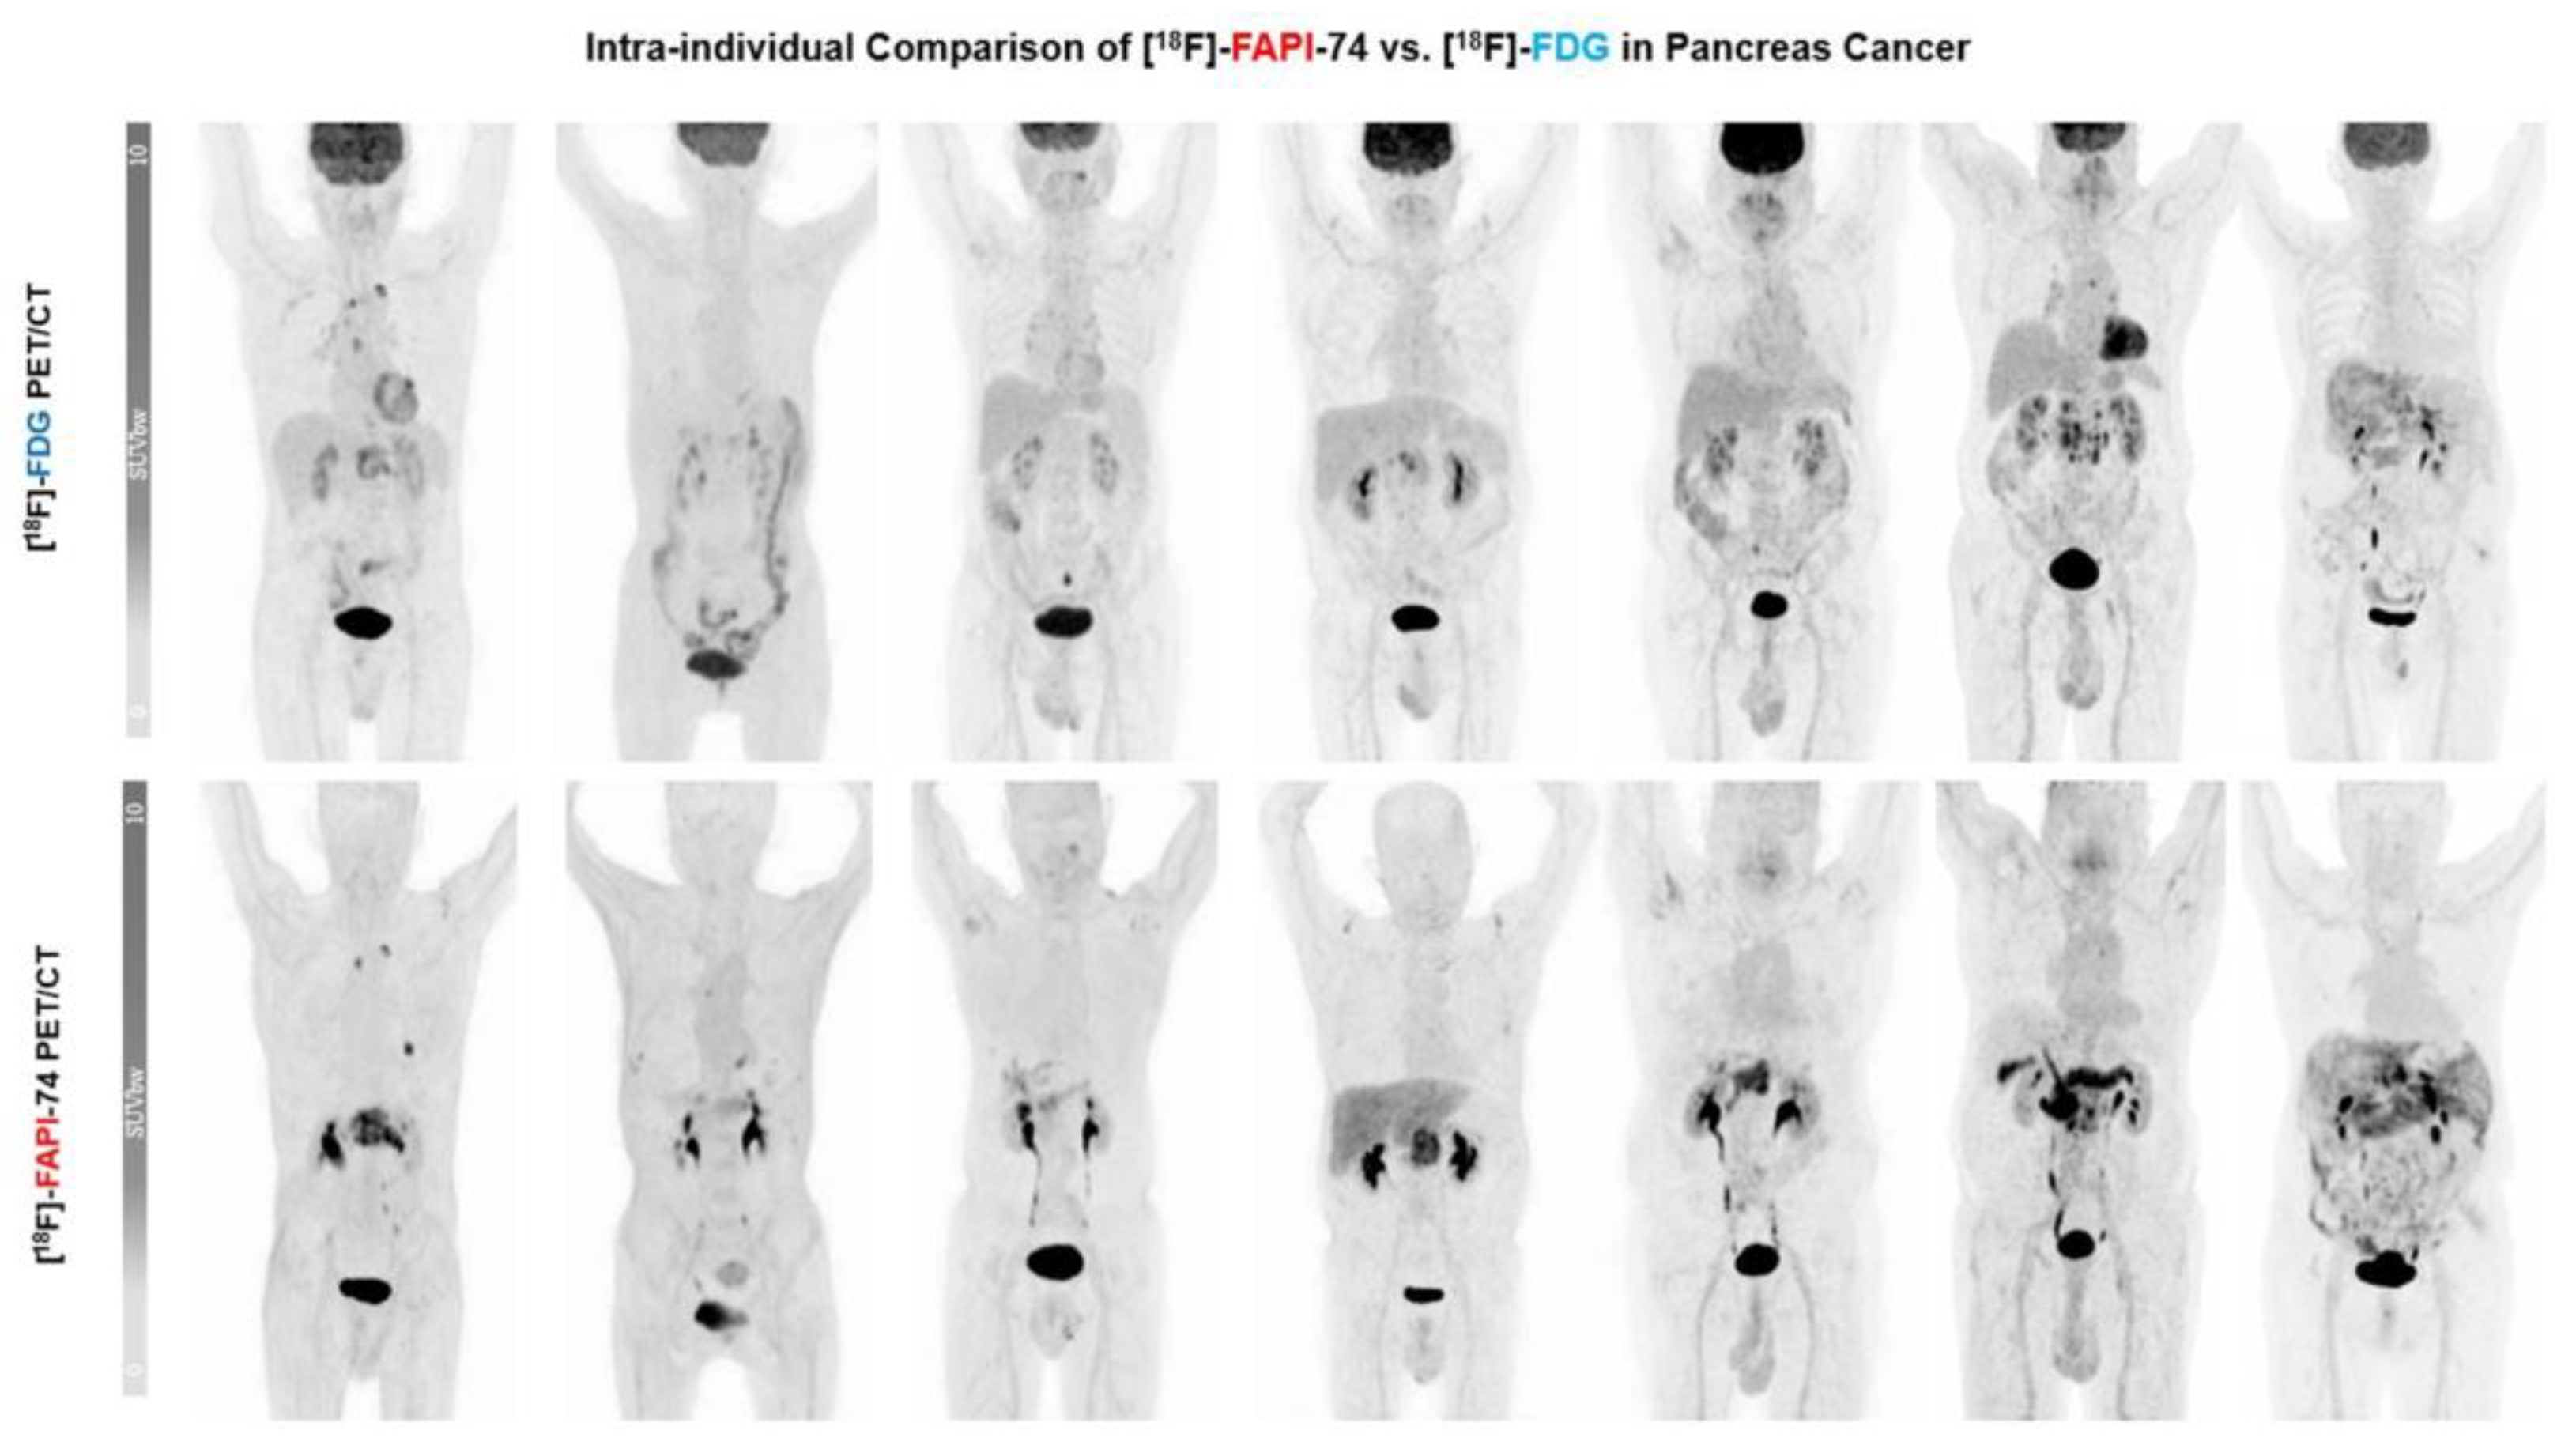

3.3. [18F]FAPI-74 Uptake in Tumor Lesions

3.4. [18F]FAPI-74 in PDAC with Confounding Pancreatitis